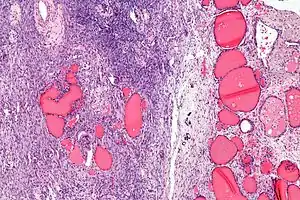

| Micrograph of a struma ovarii. Characteristic thyroid follicles are seen on the right, and ovarian stroma on the left. H&E stain. | |